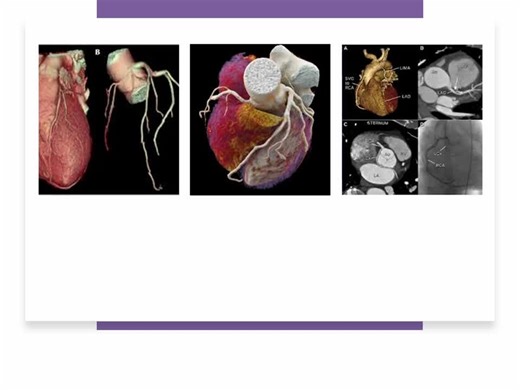

Coronary CT Angiography Procedure

Coronary CT Angiography: Optimizing Images for Clinical Practice

vumedi.com

Coronary CT Angiography Benefits

CTCA: A non-invasive imaging technique for coronary arteries | Ashish Sharma posted on the topic | LinkedIn

CT Angiography for Evaluation of Coronary Disease: Indications, Anatomy, Function, and Plaque